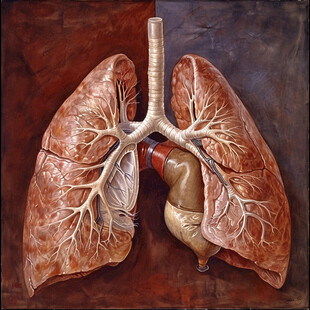

肺部结构 共享分: 200

肺部结构 共享分: 200 -